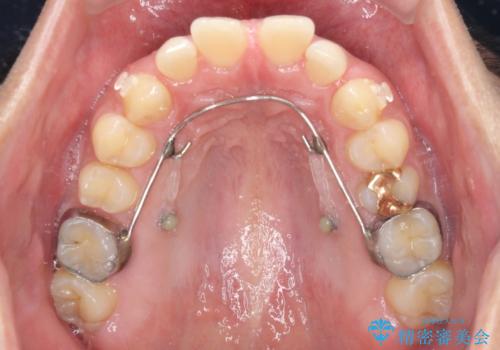

インビザライン開始前に奥歯の咬み合わせを変える補助装置は幾つかあります。

咬み合わせの強さや下顎の歯列の状態などによって、最適な補助装置を選択しています。

インビザライン単独で咬み合わせを改善することもできますが、治しきれない可能性が高いため、事前に補助装置で治しておくことは、治療の仕上がりの点で非常に重要となります。